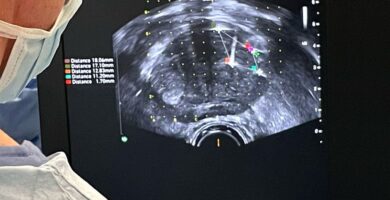

Guia operatoria Biopsia por Fusión con Robot Artemis

Aquí encontrará información útil sobre su procedimiento

Antes del procedimiento

Será necesario que se realice una preparación. Le fac...